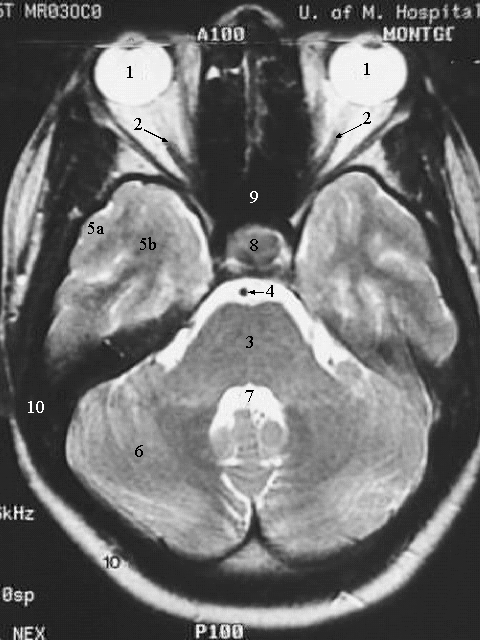

Radiology Images

Head & Neck: Head MRI Pons:

1. Eyeball

2. Optic nerve

3. Pons

4. Basilar artery

5. a. Temporal lobe gray matter.

b. Temporal lobe white matter.

6. Cerebellum

7. Fourth ventricle

8. Hypophysis

9. Sphenoid air sinus

10. Temporal bone and scalp.